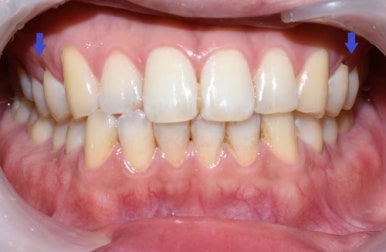

치료 전 모습으로 치아가 누렇고 착색이 있으며, 치아 패인 부분이 있음(화살표)

구강검진 후 스케일링,치아 패인곳(화살표) 떼우기, 원데이2회미백을 진행하기로 상담하였으며

아래는 첫 날 치료(스케일링, 치아패인곳 떼우기, 원데이2회미백 진행)의 전&후 사진입니다.

당일 스케일링,화살표패인곳떼우는치료,미백2회 치료

색상의 변화가 보이시죠!